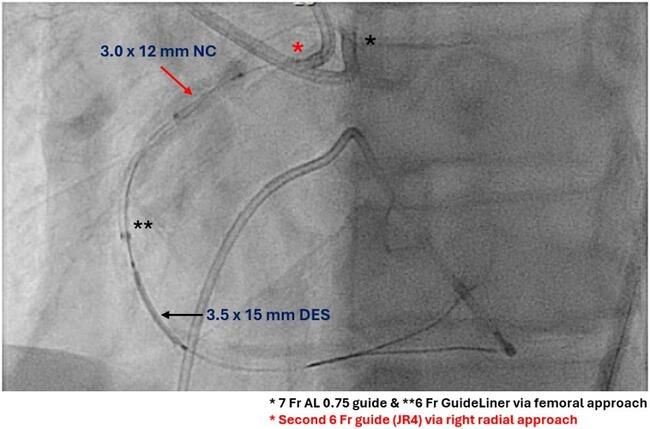

It was decided to use ping-pong guides for the modified tunnel-in-landslide technique (TILT). A second guide (6F JR4) engaged the RCA from the radial approach, and a 3.0-mm balloon was inflated in the proximal RCA to trap the 6F guide extension (GE) (Figure 3). With this maneuver, the operator was successfully able to deliver the balloons and stent (Figure 3, Video 1), followed by a larger (4.0-mm) IVL balloon. The final angiogram (after stenting the remaining RCA) showed a good result, with an intravascular ultrasound minimal stent area of 7.5 mm² (Figure 4, Video 2).